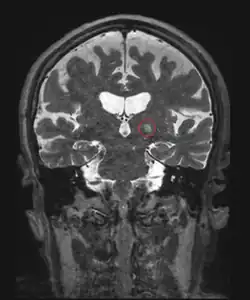

Frontal MRI four days after MRgFUS (MRI-guided high-intensity focused ultrasound): Left ventral intermediate nucleus (Vim) thalamotomy. 79-year-old man with essential tremor.

Additionally, MRI-guided high-intensity focused ultrasound is a nonsurgical treatment option for people with essential tremor who are medication refractory.[86][87] MRI-guided high-intensity focused ultrasound does not achieve healing, but can improve the quality of life by reducing the tremor manifestation.[87][88] While its long-term effects are not yet established, the improvement in tremor score from baseline was durable at 1 year and 2 years following the treatment.[89] To date, reported adverse events and side effects have been mild to moderate. Possible adverse events include gait difficulties, balance disturbances, paresthesias, headache, skin burns with ulcerations, skin retraction, scars, and blood clots.[86][87][90] This procedure is contraindicated in pregnant women, persons who have non-MRI compatible implanted metallic devices, allergy to MR contrast agents, cerebrovascular disease, abnormal bleeding, hemorrhage and/or blood clotting disorders, advanced kidney disease or on dialysis, heart conditions, severe hypertension, and ethanol or substance abuse, among others.[87] The US Food and Drug Administration (FDA) approved Insightec's Exablate Neuro system to treat essential tremor in 2016.[87]